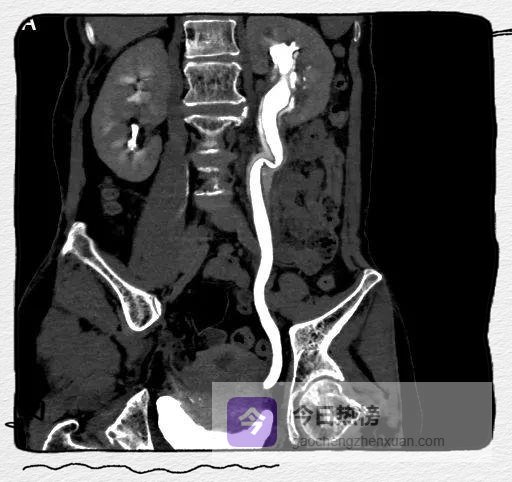

图1A

CT平扫示左肾及左侧输尿管扩张积水。

图2A

CT增强扫描呈双环及双腔改变,早期可见外腔密度增高。

图4A-C

左侧肾盂及输尿管上段呈“双环及双腔样”改变,考虑夹层形成;三维重建可清楚的观察到撕裂肾盂及输尿管的真假腔并显示撕裂范围。